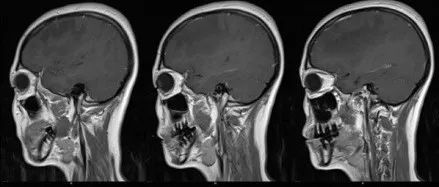

中年女性,间歇性头晕头痛2年,请诊断!

医学影像  yxyx-app  医学影像APP,打造伴随医生快速成长的影像学习社区。与影像园(Xctmr.com)一起提供最全面的影像案例库、基础(解剖、病理、影像诊断)知识、影像技术及考题等,为医生提供最佳的医学影像参考。【所属科室】神经外科【基本资料】患者,女,43岁【主诉】间歇性头晕、头痛2年,视物模糊半年,加重半月。【现病史】患者2年前无明显诱因出现头晕、头痛,为双额颞部阵发性胀痛,程度较轻,可自行缓解,伴有恶心,无呕吐,自服止痛药处理,未规律诊治,半年前无明显诱因出现视物模糊,晨起时明显,持续约15秒后自行缓解,半月前上述症状加重,转移视线时亦可出现视物模糊,持续15秒后可缓解,性质同前...